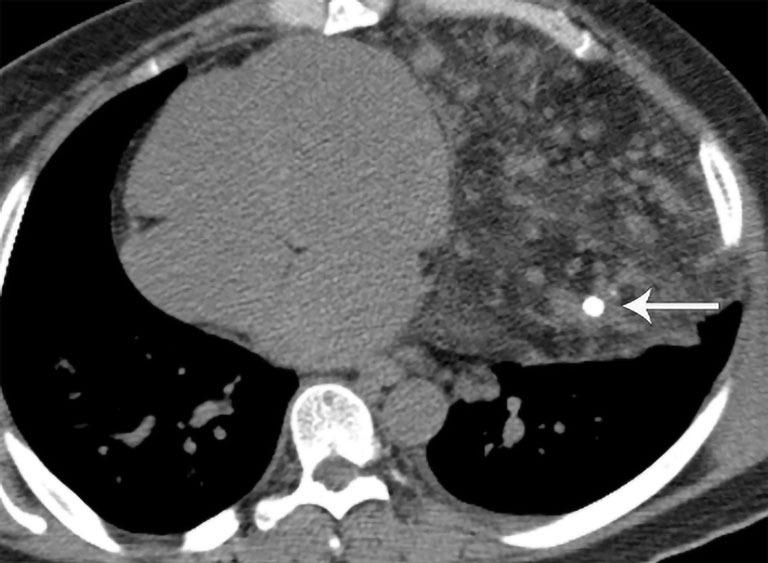

纵隔肿块及类似病变的多模态成像

Multimodality imaging of mediastinal masses and mimics.

A wide variety of neoplastic and nonneoplastic conditions occur in the mediastinum. Imaging plays a central role in the evaluation of mediastinal pathologies and their mimics. Localization of a mediastinal lesion to a compartment and characterization of morphology, density/signal intensity, enhancement, and mass effect on neighboring structures can help narrow the differentials. The International Thymic Malignancy Interest Group (ITMIG) established a cross-sectional imaging-derived and anatomy-based classification system for mediastinal compartments, comprising the prevascular (anterior), visceral (middle), and paravertebral (posterior) compartments. Cross-sectional imaging is integral in the evaluation of mediastinal lesions. Computed tomography (CT) and magnetic resonance imaging (MRI) are useful to characterize mediastinal lesions detected on radiography. Advantages of CT include its widespread availability, fast acquisition time, relatively low cost, and ability to detect calcium. Advantages of MRI include the lack of radiation exposure, superior soft tissue contrast resolution to detect invasion of the mass across tissue planes, including the chest wall and diaphragm, involvement of neurovascular structures, and the potential for dynamic sequences during free-breathing or cinematic cardiac gating to assess motion of the mass relative to adjacent structures. MRI is superior to CT in the differentiation of cystic from solid lesions and in the detection of fat to differentiate thymic hyperplasia from thymic malignancy.

纵隔可发生各种各样的肿瘤性和非肿瘤性疾病。影像学在纵隔病变及其类似病变的评估中起着核心作用。将纵隔病变定位到某个分区,并对其形态、密度/信号强度、强化情况以及对邻近结构的占位效应进行特征描述,有助于缩小鉴别诊断范围。国际胸腺恶性肿瘤研究小组(ITMIG)建立了一种基于横断面成像和解剖学的纵隔分区分类系统,包括血管前(前)、内脏(中)和椎旁(后)分区。横断面成像在纵隔病变评估中不可或缺。计算机断层扫描(CT)和磁共振成像(MRI)有助于对X线检查发现的纵隔病变进行特征描述。CT的优点包括广泛可用、采集时间短、成本相对较低以及能够检测钙化。MRI的优点包括无辐射暴露、软组织对比分辨率高,能够检测肿块跨越组织层面的侵犯情况,包括胸壁和膈肌、神经血管结构受累情况,以及在自由呼吸或电影式心脏门控期间进行动态序列成像以评估肿块相对于相邻结构的运动情况。在区分囊性病变与实性病变以及检测脂肪以鉴别胸腺增生与胸腺恶性肿瘤方面,MRI优于CT。